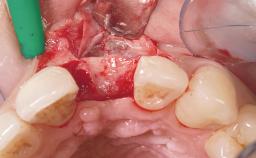

Immediate Placement of an Implant in a Maxillary Right Central Incisor Site

A 30-year-old female patient was referred to the office for the treatment of tooth 11. Her chief concern at the initial visit was to inquire, “Why is my tooth pink?” Upon clinical examination, it was determined that tooth 11 had a previous history of trauma and that the clinical crown had become noticeably pink in color as a result of internal resorption. This diagnosis was confirmed radiographically, indicating a large radiolucency involving the central and distal portions of the clinical crown. It was determined that restoration of this tooth was not possible, and that extraction was indicated. The presence of a mid-line diastema, which the patient wanted to reproduce, directed the treatment plan for tooth replacement utilizing a dental implant.

Placement Protocol Immediate implant placement

Tooth Site Maxillary incisor or canine

Socket Morphology Single-root socket

Socket Integrity Sufficient, with intact bone walls